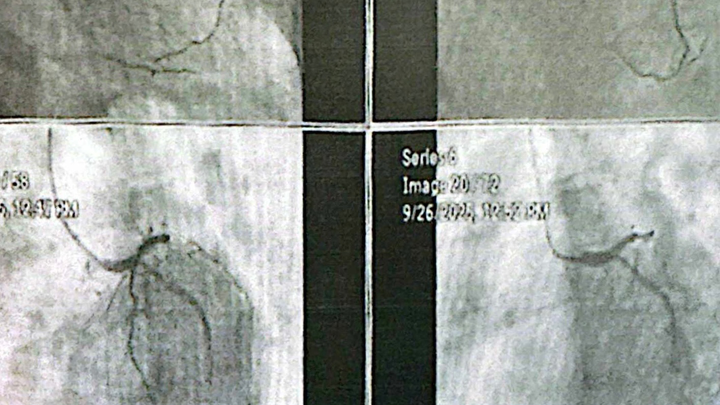

Hello everyone, my name is Aida. I'm creating this fundraiser on behalf of my sister Victoria. Her attending physician recently referred her to undergo an immediate angioplasty at the Philippine Heart Center due to alarming symptoms and test results that require urgent intervention.

In the past months, my sister had already been admitted to the hospital twice because of heart attacks with complications. Her condition has been challenging for her and heartbreaking for us to witness. The doctors had told her family that she needed this procedure as soon as possible to prevent her health from worsening.